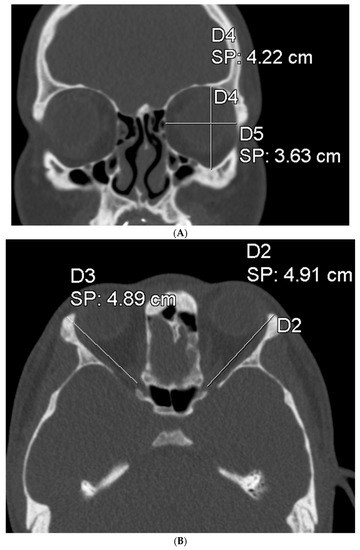

Figure 1.

On the left is a preoperative surface model of a patient with UCLP and severe midline asymmetry. On the right is the planned correction of bony asymmetry with CAD/CAM-generated patient-specific osteosynthesis for simultaneous Le Fort I osteotomy and bilateral sagittal split osteotomies.